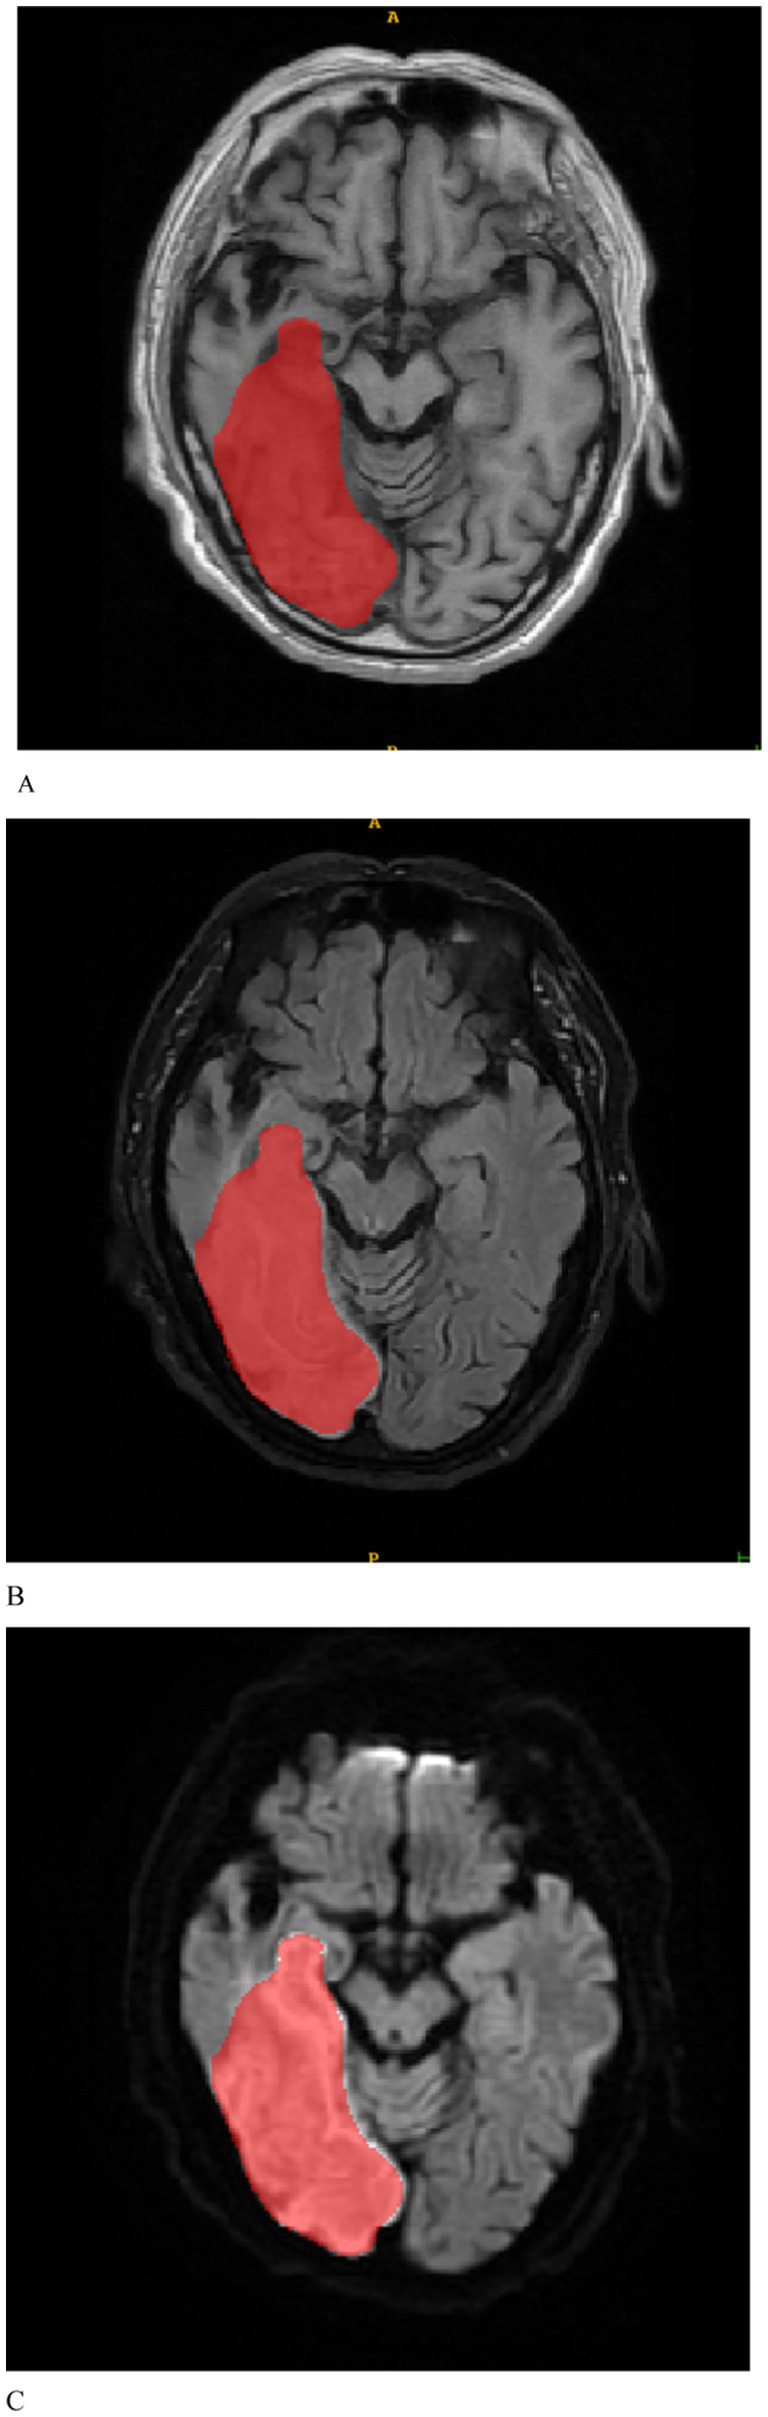

The MRI images were initially subjected to standardization procedures, including voxel resampling to 1 × 1 × 1 mm, adjustment of window width and level, N4 bias field correction, and normalization using Z-scores. Two radiologists, who were blinded to all patient information, assessed the MRI images. The axial MRI images of the enrolled patients were imported in DICOM format into the ITK-SNAP 3.8.0 software1. First, T1WI, FLAIR, and DWI sequences of the patients’ images were recorded. Given the challenges in delineating stroke lesion boundaries using T1WI and FLAIR images, stroke lesions were manually outlined on DWI images while considering the reference T1WI and FLAIR images (Figure 2). Disagreements were discussed until a consensus was reached. The software subsequently fused the region of interest for each image slice, yielding three-dimensional structural data of the lesions (volume of interest). To ensure the consistency and stability of lesion segmentation, 40 randomly selected MRI images from other patients were independently assessed by a second radiologist who applied the same methodology to outline the lesions and extract radiomics features. The intraclass correlation coefficient (ICC) was used to evaluate the consistency of the extracted features, with values exceeding 0.75 indicating good reproducibility.

Figure 2

Based on the manually delineated regions of interest for patients with stroke, (A–C) represent the T1WI, FLAIR, and DWI sequences, respectively.